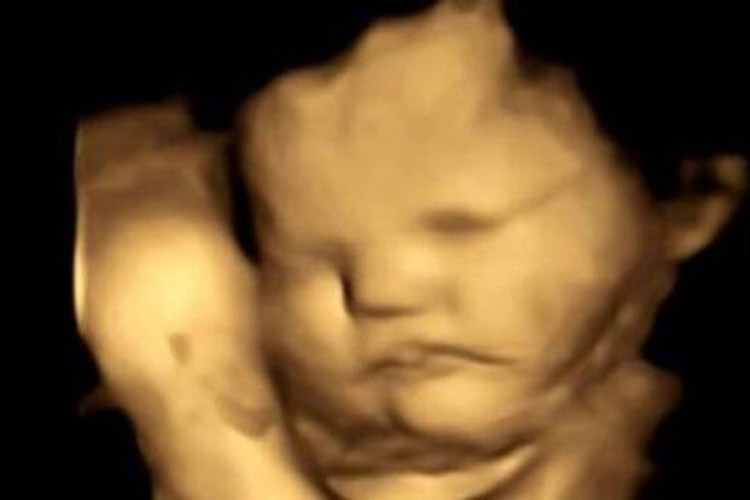

Prva studija koja je proučavala izraze lica fetusa na različite ukuse pokazala je da nerođene bebe dva puta češće imaju formiraju grimase na svom licu kada probaju kelj u odnosu na šargarepu.

Da bi ispitali da li fetusi mogu da razlikuju različite ukuse, tim je ultrazvukom snimao 70 trudnica između 18 i 40 godina starosti, koje su bile podijeljene u dvije grupe.

Trudnice u jednoj grupi su uzimale kapsulu sa keljom u prahu 20 minuta prije ultrazvuka, a one u drugoj grupi su dobijale kapsulu sa šargarepom u prahu. Sve trudnice su u periodu trudnoće imale sličnu ishranu i unos povrća.

Tim naučnika je nakon pregleda obavljao analizu svakog snimljenog kadra i posmatrao izraze lica fetusa, uključujući i kombinacije grimasa koje su izgledale kao plač ili smijanje.

Napravljeno je više od 180 ultrazvučnih snimaka na 99 fetusa, koji su skenirani u 32. i 36. nedjelji trudnoće.

Plačni izrazi lica bili su dva puta češći kada su majke konzumirale kapsule sa keljom u poređenju sa fetusima čije su majke uzimale kapsule sa šargarepom ili nisu uopšte uzimale kapsule.

U slučaju kapsula sa ukusom šargarepe, lica nerođenih beba su često dobijala izraz osmjehivanja, prenosi RTS.